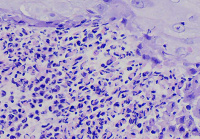

外阴多发赘生物,请教老师们,怎么报告?

性别

女

年龄

62

发现外阴数十粒丘疹样结节,伴溃疡

外阴丘疹样赘生物

灰白色组织两粒0.5*0.3cm

考虑:疱疹病毒感染

疱疹性皮炎。

符合疱疹性皮炎。